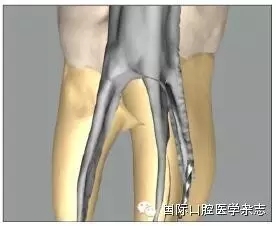

3.2.4 器械材質(zhì)類型的評估 不銹鋼K銼取出的概率略高于鎳鈦機(jī)用器械,這或許是因2類器械的錐度、橫截面設(shè)計(jì)和使用方法的截然不同所致。機(jī)用器械多為大錐度,在其旋轉(zhuǎn)運(yùn)動(dòng)時(shí),器械尖端更易鎖入根管壁。一般情況下,分離的鎳鈦器械較不銹鋼器械更難從根管中取出[14],原因包括以下幾點(diǎn):1)鎳鈦器械為旋轉(zhuǎn)運(yùn)動(dòng),更傾向于嵌入根管壁內(nèi)而難以取出[3];2)尤其在使用超聲的情況下,鎳鈦器械因溫度升高容易發(fā)生二次分離[15];3)由于鎳鈦器械有良好的可彎曲性能,分離于彎曲根管中的鎳鈦器械往往抵在根管的外側(cè)壁上而不是保留在根管的中心,增加了取出的難度[16](圖7);4)一般分離器械越長,越容易取出,因?yàn)檩^長的分離器械往往位于根管的更冠方部位,而分離的鎳鈦器械往往較小[17]。

圖 7 分離于彎曲根管的鎳鈦器械往往抵在根管外側(cè)壁,而不會(huì)保留在根管的中心